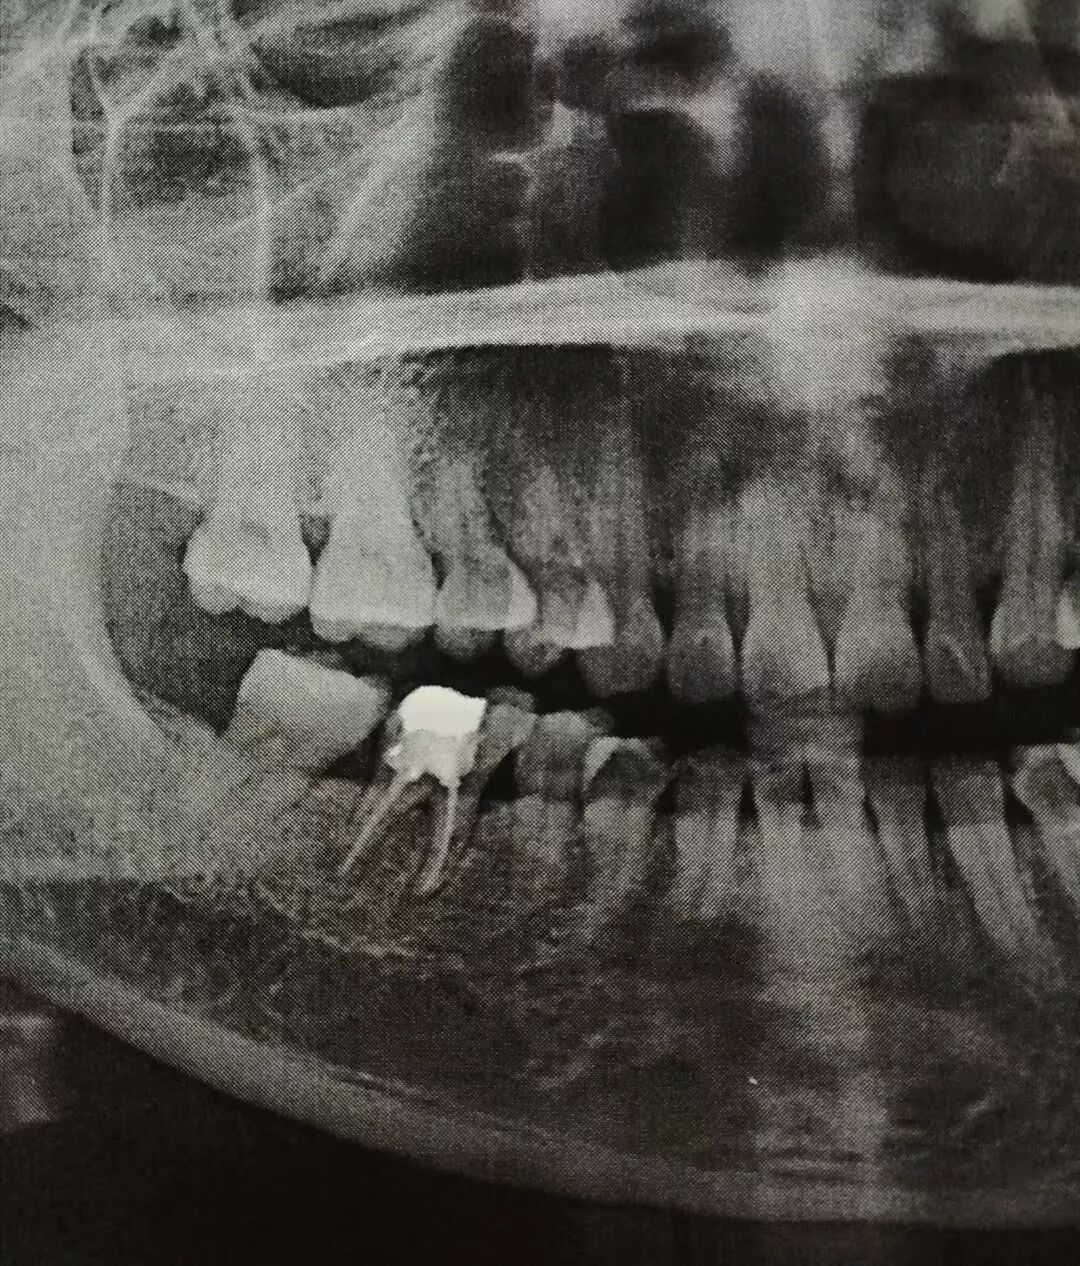

然而,中国的口腔医疗现状是,很多做完根管治疗的病人,就不愿做冠修复了,这里面的原因很多,有医患之间的不信任,或者百度搜到了烤瓷牙的负面信息,对磨牙齿的担忧及抗拒,因价格问题而揣摩医生的趋利意图,对牙齿健康的侥幸心理,不愿麻烦花时间复诊,甚至牙齿不痛就忘了此事,等等因素,不做冠修复,让失去保护的牙在口腔咀嚼中裸奔,崩裂的概率非常大,一旦裂开,只有拔牙,然后首选种植牙修复,根管治疗白做不说,钱白花,后期还得十几倍的花费,在牙科,“早知今日,何必当初”的病例,从来都不在少数。这是某天下午连续拔除的两例未做冠修复的折裂牙,可窥一斑。